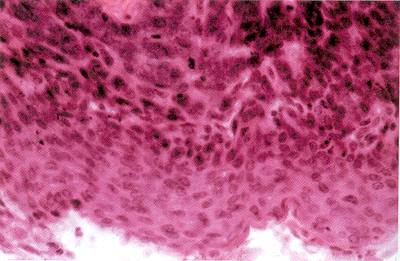

睑基底细胞癌

上皮细胞增生排列较紊乱,但也有上皮细胞规则地排列成栅状或环状。细胞大小不太一致,染色深,有丝分裂多见。